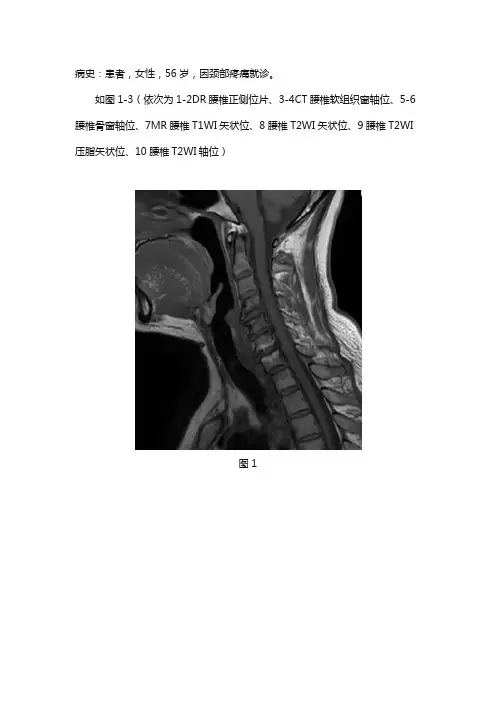

病史:患者,女性,56岁,因颈部疼痛就诊。

如图1-3(依次为1-2DR腰椎正侧位片、3-4CT腰椎软组织窗轴位、5-6腰椎骨窗轴位、7MR腰椎T1WI矢状位、8腰椎T2WI矢状位、9腰椎T2WI 压脂矢状位、10腰椎T2WI轴位)图1图2图3基础解剖影像:椎骨幼年为32或33块,分为颈椎7块,胸椎12块,腰椎5块,骶椎5块,尾椎3-4块,成年后5块骶椎合成骶骨,3-4块尾椎合成尾骨。

影像诊断:如图1-3所示。

影像描述:MR:颈椎椎体序列正常,生理曲度存在。

颈椎椎体边缘变尖,呈唇样改变。

颈4-5、5-6、6-7椎间盘向四周膨出,局部向后突出,硬膜囊受压。

颈6-7椎体相邻终板见斑片状短T1长T2信号,压脂像呈低信号。

颈4椎体下缘见限局性凹陷压迹。

影像诊断:颈4-5、5-6、6-7椎间盘膨出并突出。

颈6-7椎体脂肪变性。

颈4椎体许莫氏结节。

分析思路:本例从临床病史、年龄、部位、形态等方面进行具体分析如下:1.临床病史和年龄:老年女性,因颈部疼痛就诊。

中老年患者提示退行性改变。